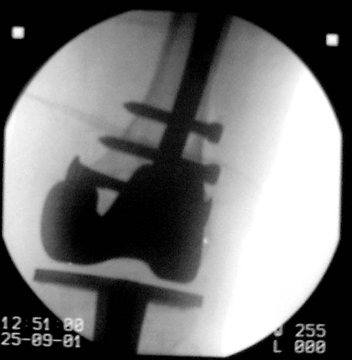

"Gamma-Nagel

Fehlstellung""Asche´s Zielgerät"